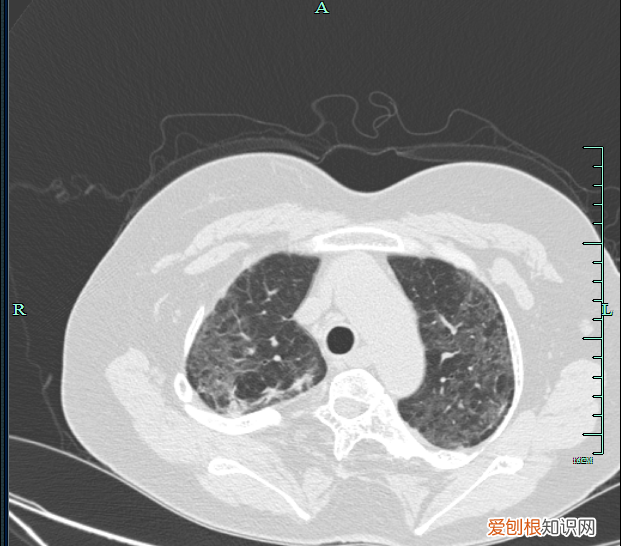

治疗前胸部CT可及双肺斑片状密度增高影

文章插图

治疗后对比病灶较前明显吸收